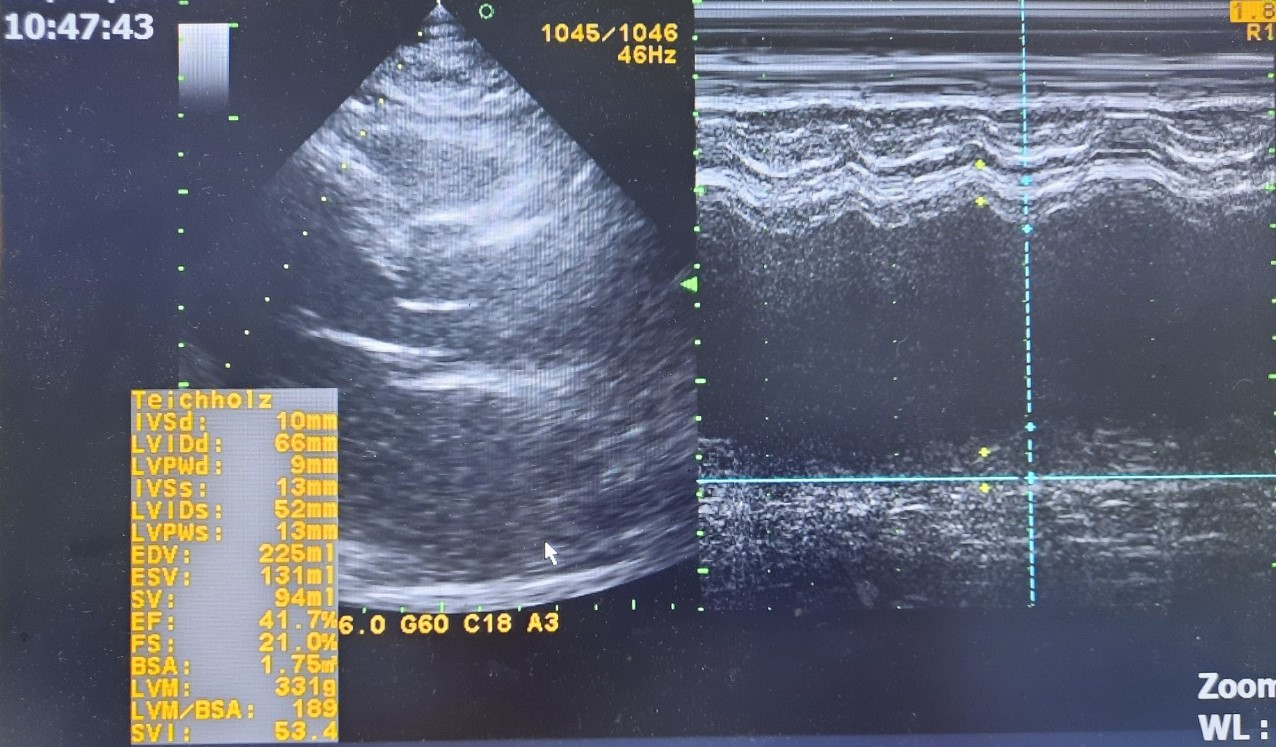

Tiếp nhận bệnh nhân trong tình trạng tim loạn nhịp hoàn toàn, mệt mỏi, khó thở nhiều, phổi RRPN giảm, nhiều hạt tophy tại khuỷu tay, bàn tay, gối, cùng cụt, da mỏng, giãn tĩnh mạch dưới da. Qua thực hiện các xét nghiệm cận lâm sàng cần thiết, phát hiện người bệnh có sỏi lớn ống mật chủ đoạn thấp sát chỗ đổ vào tá tràng gây giãn đường mật trong và ngoài gan. Kèm theo siêu âm tim buồng tim giãn lớn, chức năng tâm thu thất trái giảm nhiều, tăng áp lực động mạch phổi, nguy cơ cao trong quá trình gây mê và phẫu thuật, chưa kể các bệnh lý nền phức tạp khác: Đái tháo đường, Gout mạn biến chứng lên các khớp chi dưới, Suy thượng thận do thuốc.

- Hình ảnh siêu âm tim của người bệnh lúc tiếp nhận